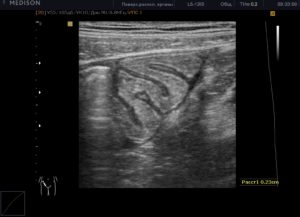

Как делают УЗИ кишечника ребенку и взрослому? Наиболее распространенная трансабдоминальное УЗИ проводится, как правило, в 3 этапа. На первом — пациент укладывается на спину, осуществляется сканирование при пустом кишечнике.

Затем человек ложится на бок и вводится жидкость, предназначенная для полного заполнения кишечника (порядка 2-2,5 л). Проводится УЗИ с заполненным органом.

Наконец, на третьем этапе кишечник очищается, и опять обеспечивается сканирование уже очищенного органа.

Чаще всего, он имеет такой состав: глицерин, тетраборнокислый натрий, сополимер стирола с малеиновым ангидридом, вода. При проведении процедуры врач-сонолог дает команды на режим дыхания, его задержку, переворот на бок или спину и т.

д.

При проведении исследований на толстой кишке жидкость в кишечник заливается через катетер диаметром порядка 7-6 мм, который вводится через анальное отверстие на глубину 4-6 см. Если обследуется прямая кишка, то заполнению подвергается мочевой пузырь, что позволяет отодвинуть петлю тонкой кишки.